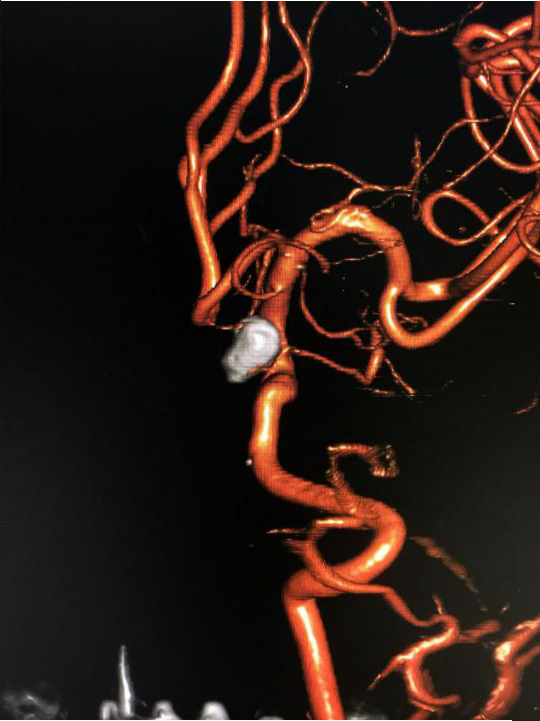

(治疗后三维造影)

入院后第二天,赵师傅被送入杂合手术室,脑血管病组团队医师们登台手术。医生们从赵师傅右股动脉穿刺,将导丝从股动脉、腹主动脉、胸主动脉一路插至颅内载瘤动脉,再运用微导管技术将弹簧圈送到动脉瘤腔内,栓塞瘤腔,在主干血管内置入一枚支架,稳固弹簧圈的同时保留了正常血管的血流。经两个小时手术,赵师傅脑内的动脉瘤被完全填塞封堵。

退休多年的赵师傅近半年出现了头痛、头晕等症状,但并未引起特殊重视。除高血压外,赵师傅没其他毛病,况且他一直规律口服降压药,血压控制良好。直至近日,赵师傅头痛、头晕发作越发频繁,这才在家人的陪同下到绵阳市第三人民医院神经外科就诊。经CT血管成像检查,发现赵师傅脑内暗藏一个“不定时炸弹”----颅内动脉瘤,而且该动脉瘤是颅内主干血管上的宽颈动脉瘤,临床上将之归类为复杂动脉瘤类型。